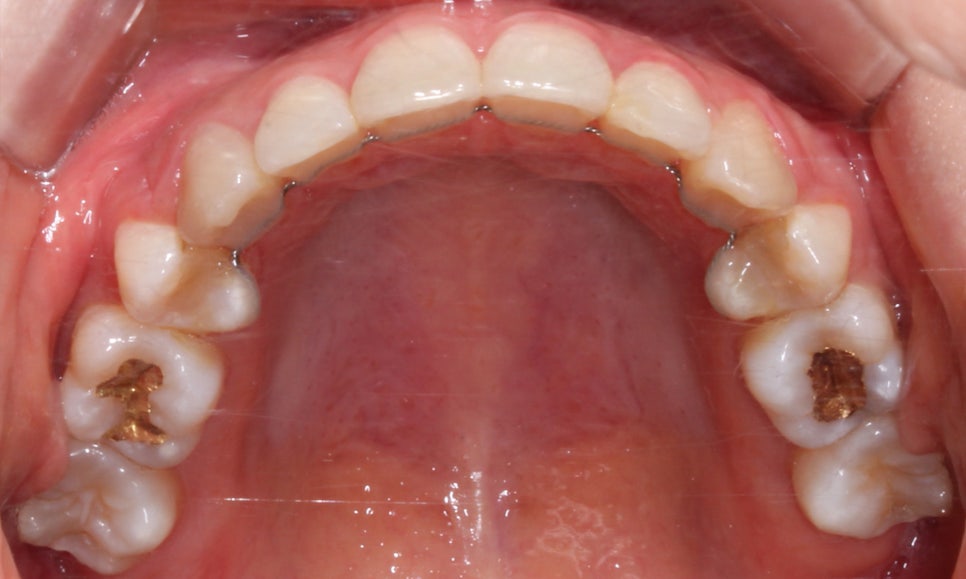

송곳니덧니 case의 상악 교합면 사진을 보시면

송곳니의 위치가 심하게 어긋나 있는 모습을 볼 수 있습니다.

부분교정의 경우 교정장치 부착의 기준이 되는

송곳니(견치)의 위치가 큰 영향을 받기 때문에

위의 Case처럼 기준치의 위치가 틀어진 경우

부분교정보다는 전체교정을 추천드립니다.